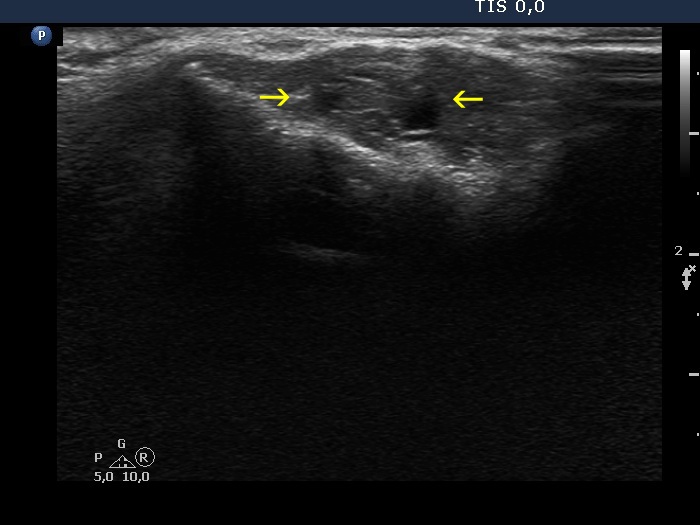

The operated thyroid - case 1524

Eleven years after the surgery (ultrasonographic picture 6b)

A few cm above the left thyroid bed, longitudinal scan. Yellow arrows point to the cystic lesion within the muscle.